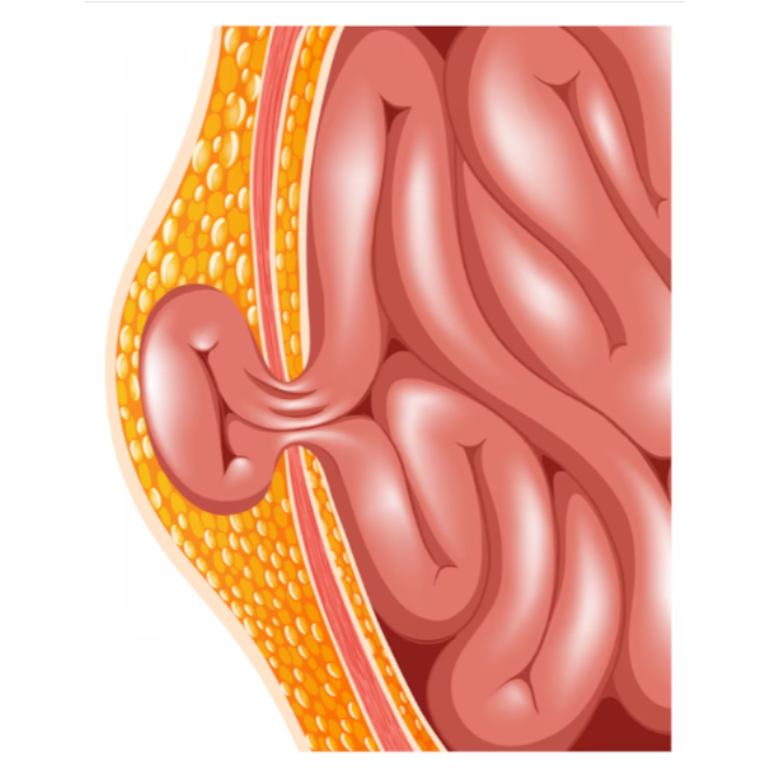

A hernia occurs when an internal organ pushes through a weak spot in the muscle, causing pain and swelling. At Dr Bharat Oza-Best General Laproscopy Surgeon PCMC in Punawale, hernia treatment is provided through advanced laparoscopic procedures.

Laparoscopic hernia surgery involves smaller incisions, which leads to less discomfort and a faster recovery compared to open surgery. This modern approach is highly effective for inguinal, umbilical, and incisional hernias, ensuring long-term relief and reduced risk of recurrence.

Patients benefit from shorter hospital stays, less scarring, and quicker return to normal activities. With precise techniques and experienced surgical care, hernia repair has become much safer and more reliable.